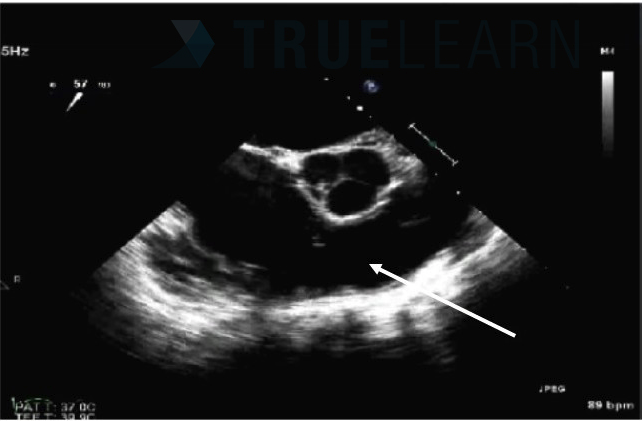

Arrow is Pointing at What Structure?

What is this view?